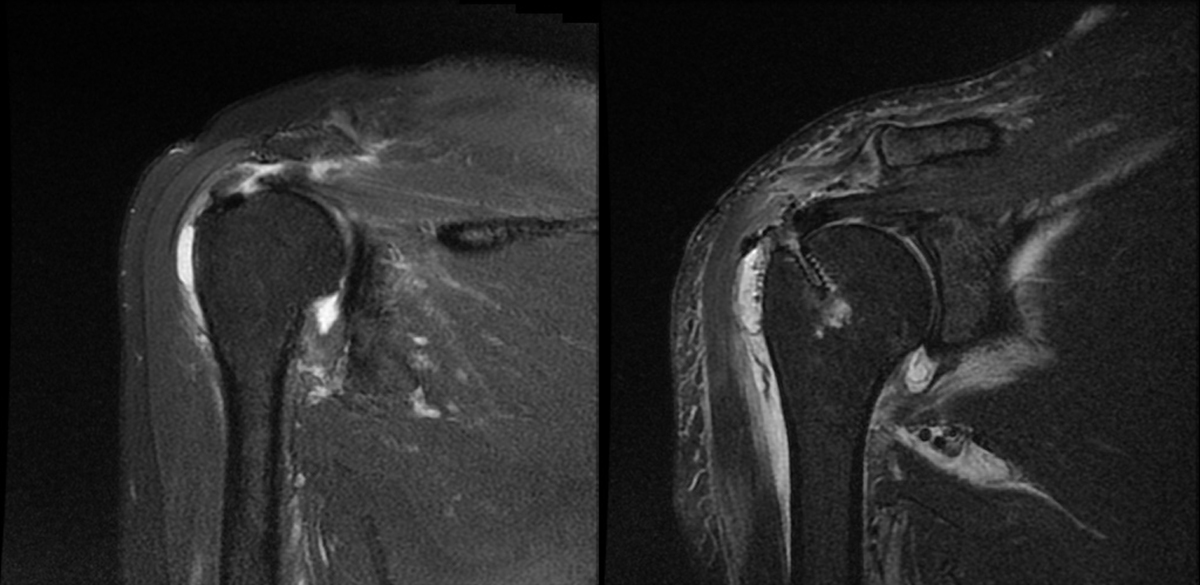

회전근개 파열의 원인은 다양하다. 노화로 인한 퇴행성 변화가 가장 흔하지만, 젊은 층에서는 외상이나 무리한 운동, 반복적인 어깨 사용으로 발생한다. 어깨는 혈액순환이 좋지 않아 한 번 손상되면 자연 치유가 어렵기 때문에 조기 진단이 중요하다. 단순 X-레이로는 힘줄 손상을 확인하기 어려워 초음파나 MRI 검사를 통해 정확한 상태를 파악한다.

회전근개 파열 수술 전/후 회전근개 봉합술은 관절내시경을 이용해 시행한다. 절개 부위가 작고 출혈이 적으며, 수술 후 통증이 덜한 게 장점이다. 카메라를 통해 내부를 직접 관찰하며 파열된 힘줄을 봉합하고, 필요 시 견봉성형술을 함께 시행해 어깨의 구조적 마찰을 줄인다. 봉합 방식에는 일렬봉합, 이열봉합(교량형 봉합) 등이 있으며, 교량형 봉합은 힘줄과 뼈를 밀착시켜 재파열 위험을 줄이는 효과가 있다.